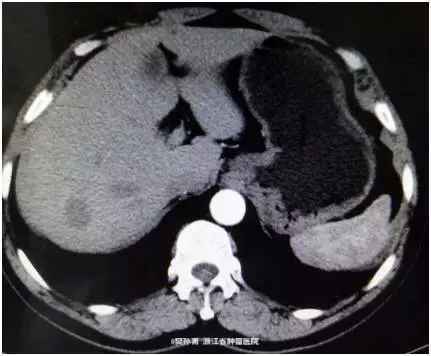

查体:心肺查体阴性,腹平软,无腹壁静脉曲张,全腹无压痛、反跳痛,腹部无包块。肝脏未触及,脾脏未触及,Murphy氏征阴性,肝、肾、脾无叩击痛,无移动性浊音。肠鸣音正常。 肿瘤标志物阴性。 CT表现:动脉期:肝包膜光整,肝脏形态正常,肝右叶可见低密度结节。大小约1.8*2.4 cm。边界模糊。门脉期:病灶强化幅度减低,边界较动脉期清晰。延迟期:病灶仍呈低密度。肝内胆管不扩张,肝门结构清晰自然,胆囊不大,壁光滑,腔内未见明显异常。脾脏、胰腺、胃、腹膜后未见明显异常。